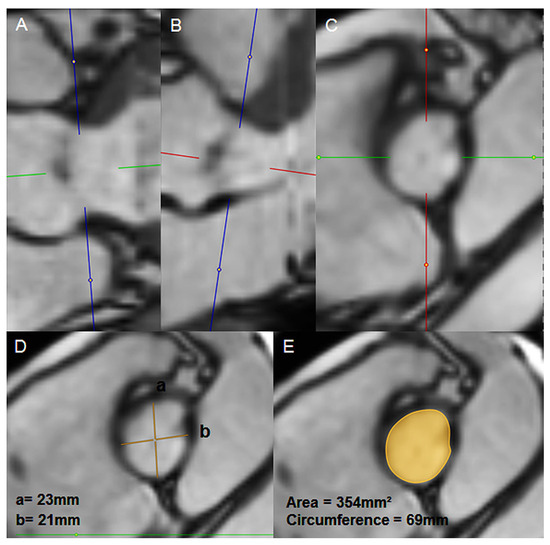

Ischaemic type ECG-modifications are not always correlated to cardiac causes. We present a case of a 63-yearold man with metastatic kidney carcinoma who had ECGabnormalities suspicious for myocardial ischaemia due to a biliary problem, which were com...